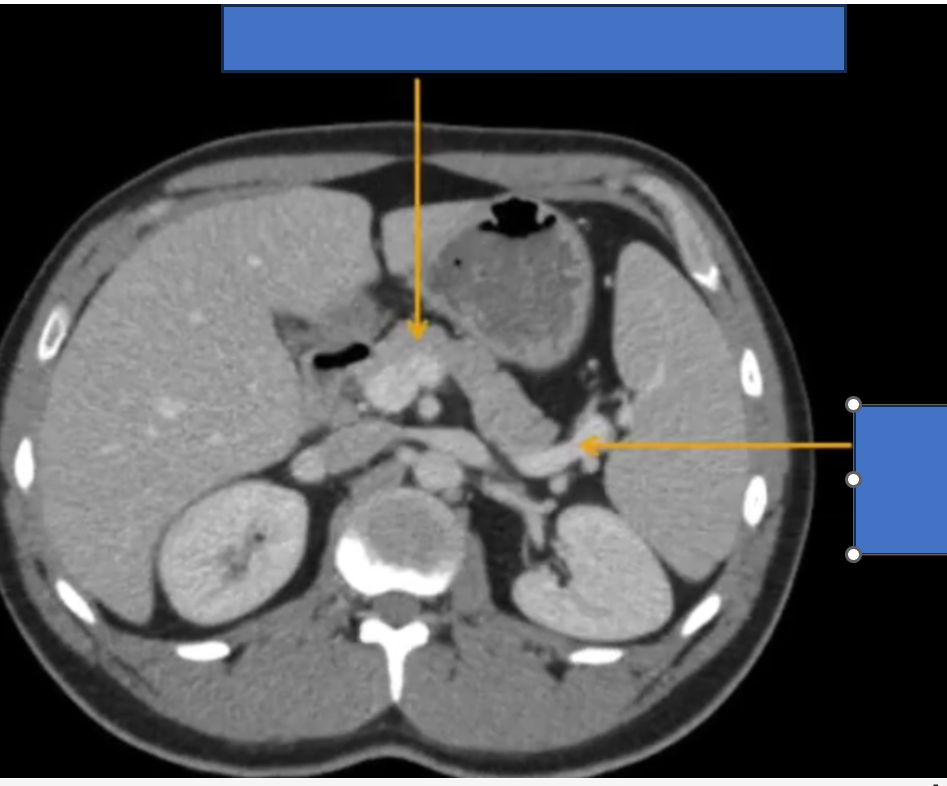

TM gan ở đâu? TM chủ dưới ? ĐM chủ?